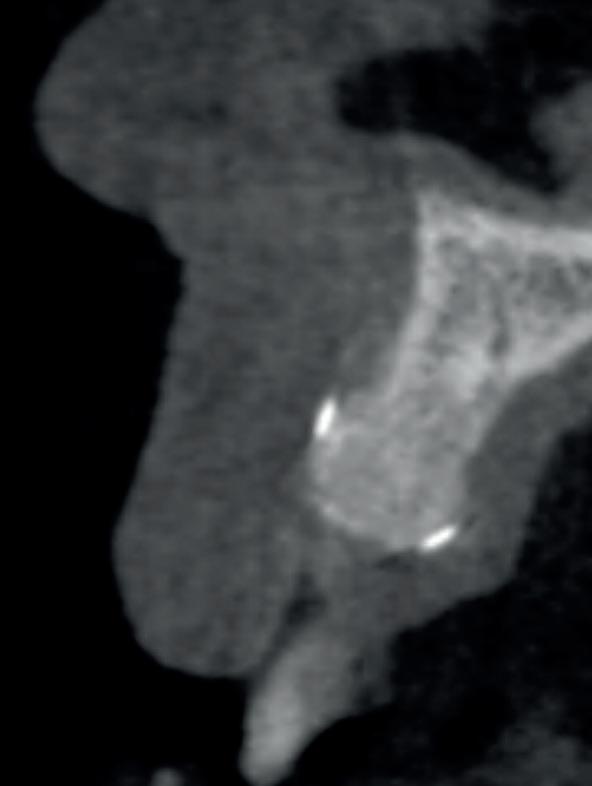

Casus

In deze casus is extractie van de 37 geïndiceerd in verband met een fistel en restpockets, zoals zichtbaar op de röntgenfoto’s (afbeelding 1). Duidelijk te zien is de forse peri-apicale ontsteking en het botverlies bij de 37, dat zowel richting buccaal als linguaal doorloopt. De 37 wordt atraumatisch verwijderd. Er is aan de linguale zijde veel bot verloren en er is sprake van een perforatie aan de buccale zijde.

Er wordt besloten om botmateriaal te plaatsen in de extractie-alveole. Vervolgens wordt het afgesloten met een titanium versterkt d-PTFE membraan (afbeelding 2). Na vier weken wordt het membraan verwijderd.

Zes maanden na extractie wordt het implantaat 37 geplaatst. Er is sprake van een goede genezing en de processushoogte en -breedte zijn behouden en opgebouwd. Ook is er zichtbaar gekeratiniseerd weefsel

1 2 Ridge preservation met d-PTFE membranen 35

gewonnen. De wond kan na het plaatsen van een healing abutment primair gesloten worden (Afbeelding 3a-3d).

In afbeeldingen 4a-c is het resultaat drie maanden na het plaatsen van het implantaat te zien. De genezing is volledig en de verwijzer kan de suprastructuur vervaardigen (afbeelding 4a-4c).

In afbeeldingen 5a-d is de implantaatkroon 37 te zien, twee jaar na plaatsing. Op de röntgenfoto is herstel van zowel corticaal als spongieus bot te zien. (De CB-CT was vervaardigd in verband met implantologische indicatie in het naastliggende gebied).

Deze casus illustreert dat er op een voorspelbare manier een ridge preservation procedure uitgevoerd kan worden met een d-PTFE membraan en er daarna voorspelbaar geïmplanteerd kan worden.